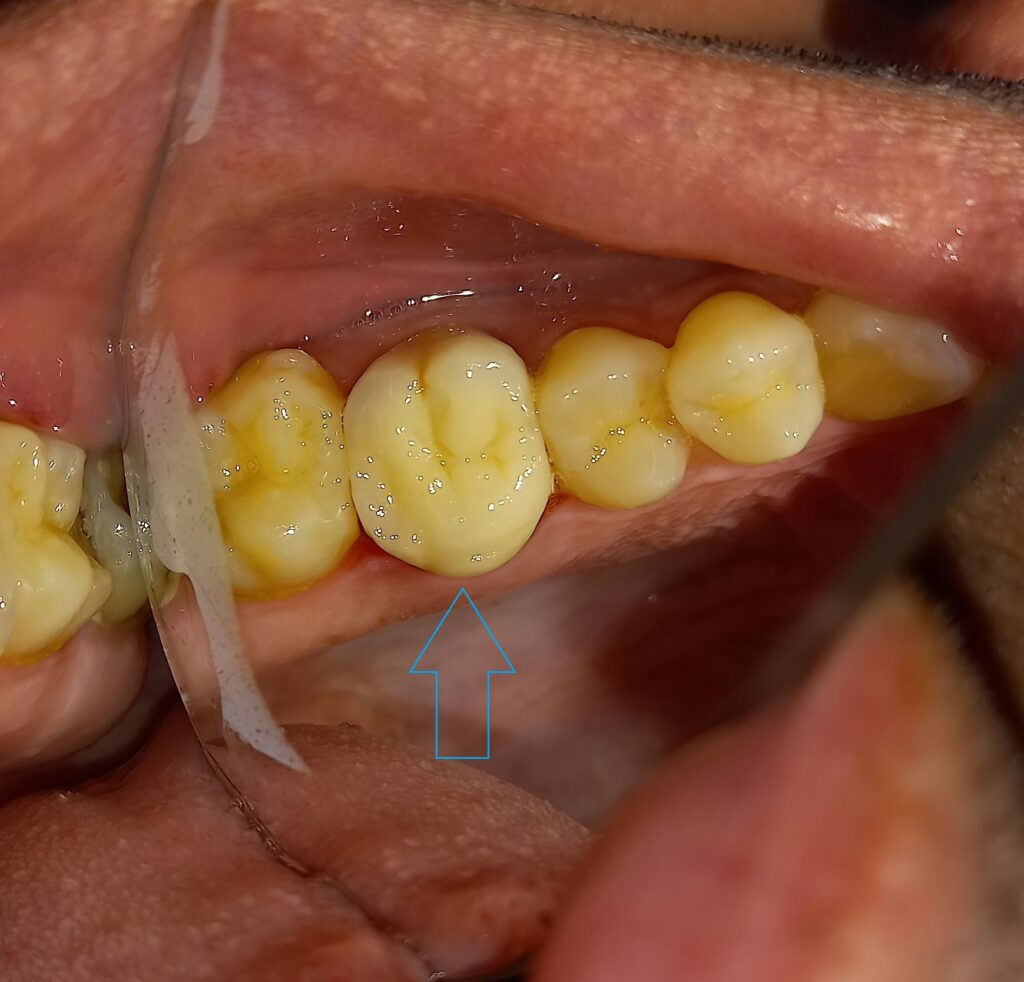

Ο ασθενής είχε καιρό ένα δόντι (άνω αριστερός γομφίος) που τον πονάει. Μετά την κλινική και ακτινογραφική εξέταση προέκυψε οτι το δόντι χρειαζόταν απονεύρωση και στη συνέχεια θα έπρεπε να καλυφθεί με θήκη γιατι είχε μεγάλο οδοντικό έλλειμμα.

ΜΕΤΑ